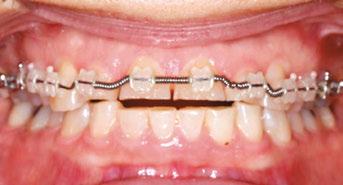

Figures 7-10: Images with braces, with and without coils, facial and maxillary occlusal views

The orthodontic treatment plan was to bond upper and lower Ormco Symetri brackets (bidimensional prescription) and intrude teeth Nos. 7-10 along with lower anterior (teeth Nos. 23-26) to establish better overbite and overjet for restorative work. Due to the loss of height of her anterior teeth, the interproximal contacts had also moved gingivally, which decreased the width of the anterior teeth (height-to-width ratios were off). In order to establish better crown ratios, the

plan was to open space mesial and distal to teeth Nos. 7-10 with open coil springs.

Though she had a rather deep bite, the Ormco Symetri bracket was low-profile and petite enough to bond the entire upper and lower braces the same day. She had no occlusal interferences with the brackets, and bite turbos were not required. The Symetri bracket’s rounded contours were comfortable to the patient, and she liked that the brackets blended with her tooth shade and met her esthetic requirements. She reported adjusting to the braces easily. The initial wires were light, 0.014 nickel-titanium archwires, and we gradually progressed into rectangular, 0.16 x 0.22 stainless steel wires for finishing. Coils were added mesial and distal to teeth Nos. 7-10 to improve the width-tolength ratios of the crowns, and teeth Nos. 7-10 were stepped up gradually to intrude them. Ideally, gingival margins of teeth Nos. 8 and 9 should be at the level of tooth No. 6 and 11, while teeth Nos. 7 and 10 should be about 1.5 mm lower5 than the centrals. As the maxillary anterior teeth were intruded, and spaces were introduced mesial and distal, the incisal angulation of the teeth also increased. This can be protective for people with a history of bruxing, in addition to leaving more inter-incisal clearance for the restoring dentist.